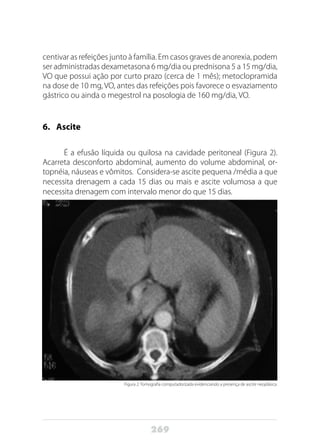

O diagnóstico precoce é difícil, especialmente devido a locali-

zação deste órgão, porém quando há suspeita de adenocarcinoma do